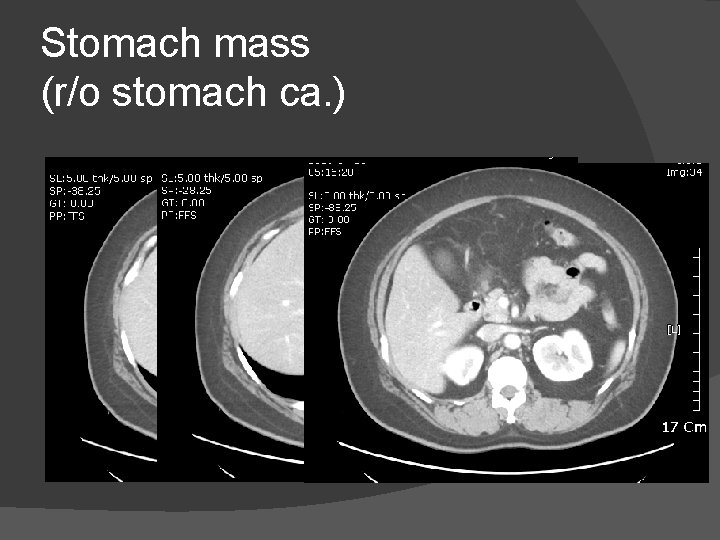

Stomach mass (r/o stomach ca. )